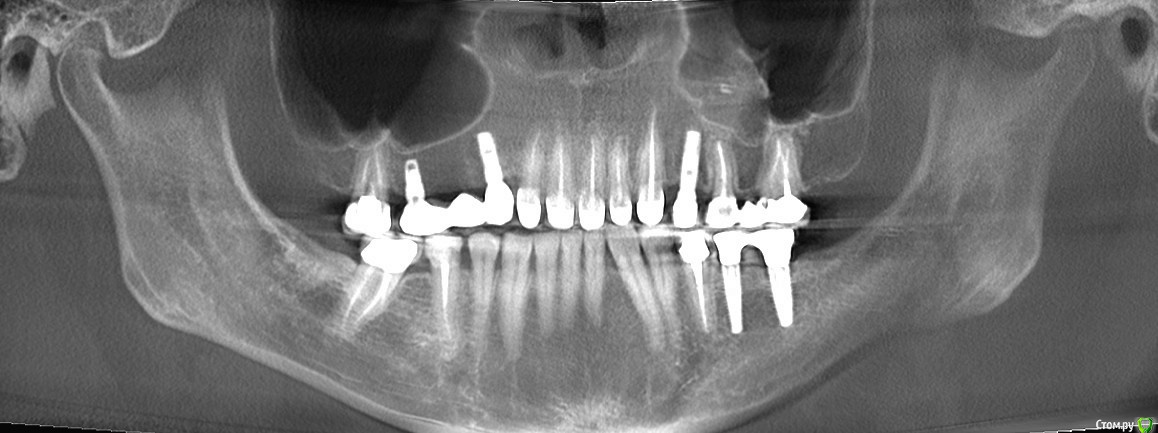

Alexandr_doc Опубликовано 26 сентября, 2018 Автор Поделиться Опубликовано 26 сентября, 2018 Прошу извинить за задержку. Прикладываю срезы со свежего КТ. Поступили предложения о хир удлинении, на мой взгляд это в данной ситуации очень рискованно. Ссылка на комментарий

kramer Опубликовано 26 сентября, 2018 Поделиться Опубликовано 26 сентября, 2018 Может, прозвучит банально, но нет смысла резцы вывести из окклюзии? По КТ плотный контакт с антагонистами Ссылка на комментарий

Alexandr_doc Опубликовано 26 сентября, 2018 Автор Поделиться Опубликовано 26 сентября, 2018 Я думаю в скором времени я буду вполне рассматривать варианты выведения зубов из окклюзии ( насколько это возможно ) или снятия коронок на некоторое время, например на день с колпачками из композита Ссылка на комментарий